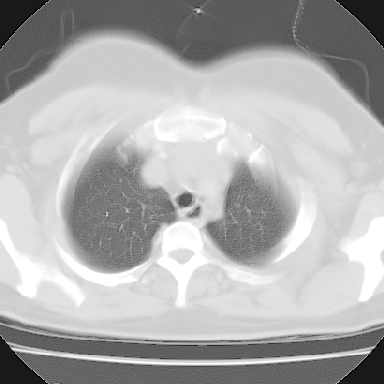

左下肺肿块影,内可以见小泡征,并见厚壁空洞形成,洞内缘凹凸不平,可见壁结节。靠近胸膜侧可见胸膜凹陷征。左侧胸腔内可见少量低密度积液影。右肺可见两处高致密的小结节影。

考虑:左下肺周围型肺癌伴右肺转移

偏心厚壁空洞壁结节

并右肺转移!病史肯定较长,考虑低分化磷癌可能.等待手术结果.

支持。另外,双侧腋下似见增大淋巴结影,有侧乳腺4、5点处皮下高密度结节影是什么?食管中下段有没有问题?病人比较年轻,因此诊断恶性肿瘤要慎重,多结合临床和其他检查,多考虑一些,也可短期抗炎治疗后复查。

右肺多发小结节影,边界清楚,符合转移瘤的特点;2、左下肺偏心性空洞影,右侧乳腺内高密度影,需要查体除外右侧乳腺肿瘤;3、腋窝淋巴结肿大,考虑转移。